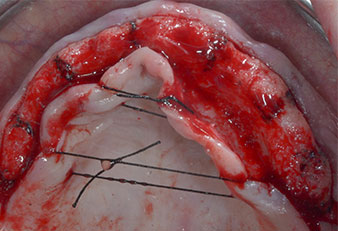

Tres años después, llegó el momento de colocar una prótesis del mismo tipo en el maxilar superior. Basándose en una planificación mediante tomografía computarizada de haz cónico (CBCT, por sus siglas en inglés), se evitó la necesidad de realizar una elevación del seno utilizando implantes cortos, mientras que una plantilla quirúrgica sirvió para transferir las posiciones planificadas al borde alveolar (figuras 1 y 2).

Fig. 1: Vista preoperatoria del borde maxilar, con las posiciones del implante marcadas con la ayuda de una plantilla quirúrgica de plástico. Debido a la baja altura del borde, se planificaron implantes posteriores supercortos.

Fig. 2: Después de la incisión en la zona crestal media y de la preparación de colgajos mucoperiósticos, las posiciones del implante se transfirieron al hueso.